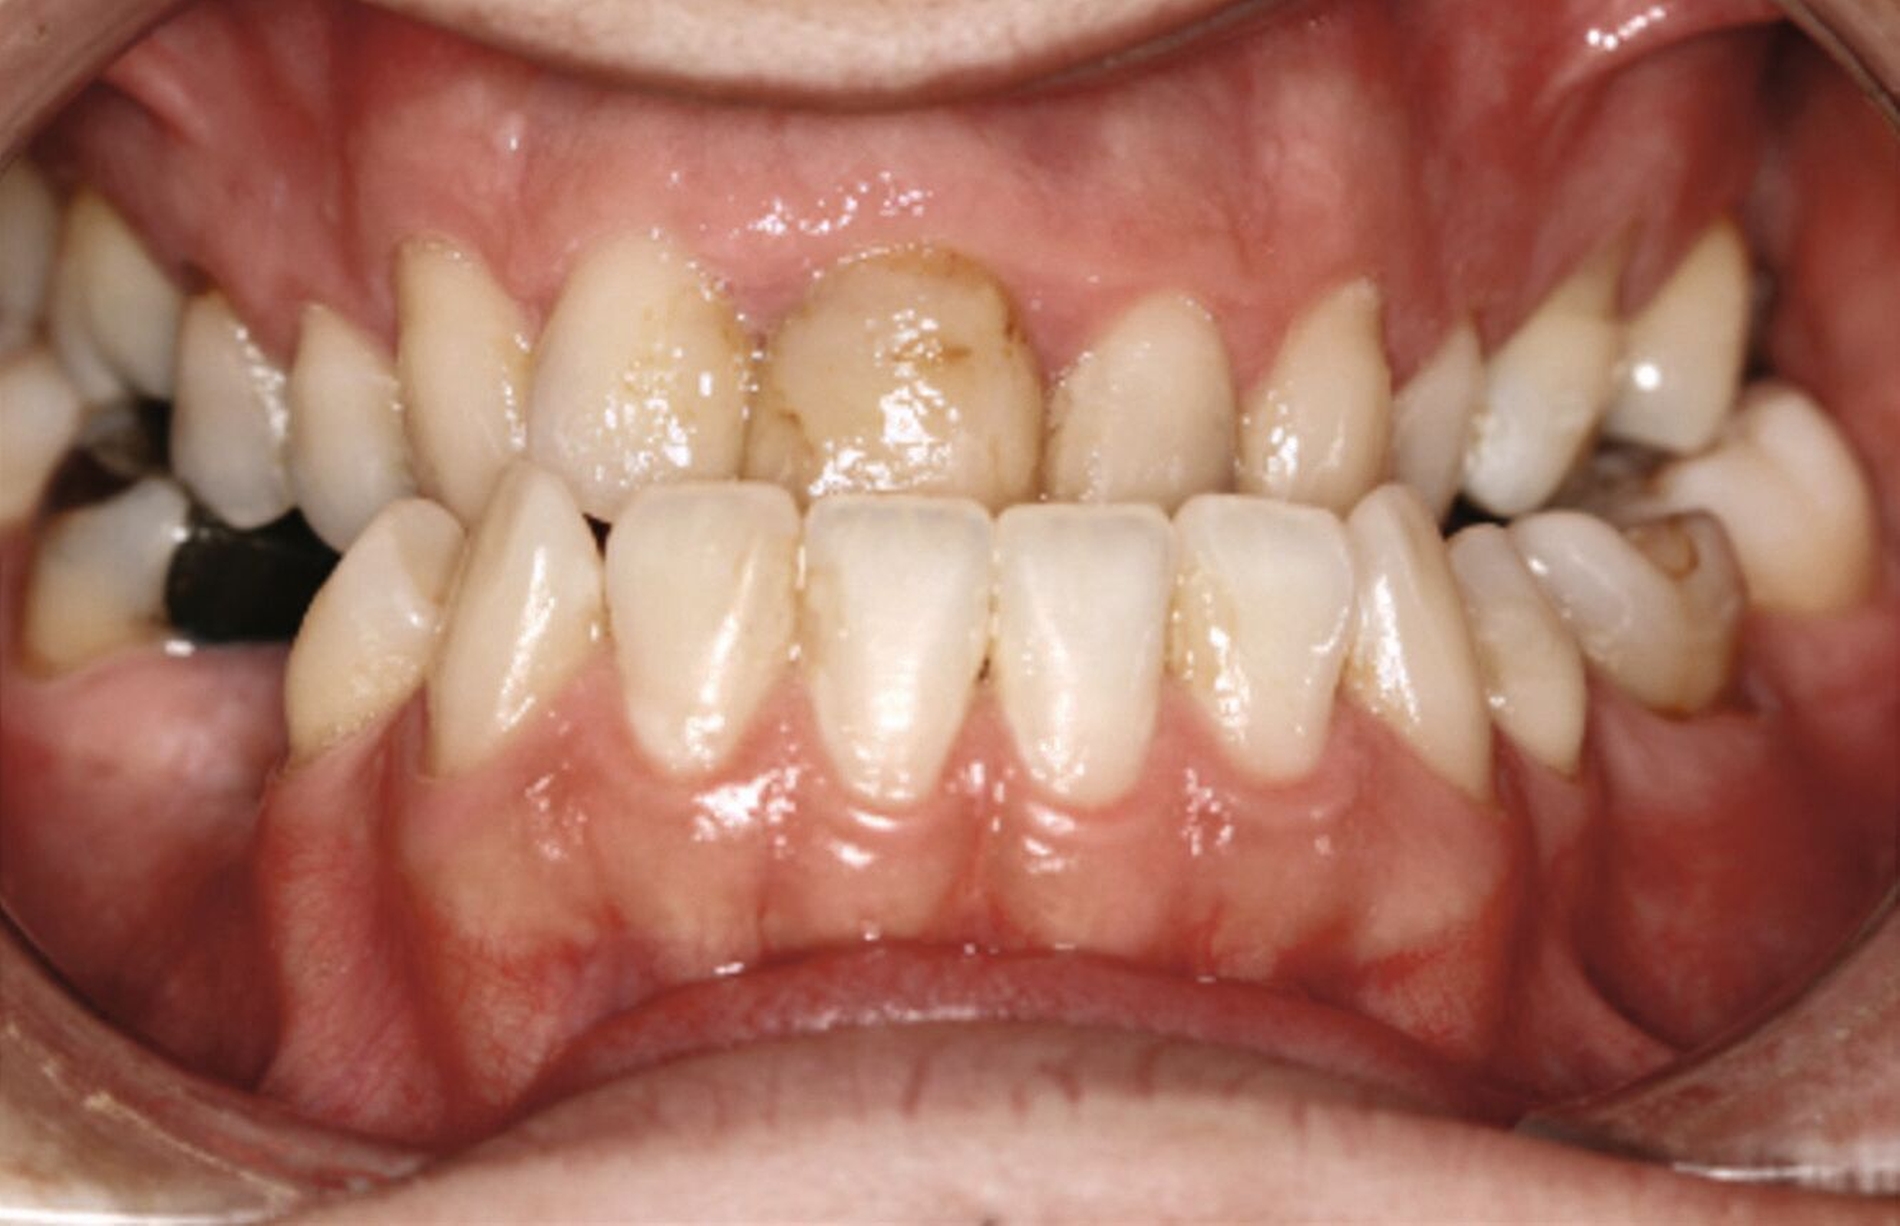

Ein 25-jähriger Patient stellte sich mit dem Wunsch nach Optimierung seines Erscheinungsbildes und seiner Kaufunktion in der kieferorthopädischen Praxis vor (Abbildung 1). Klinisch zeigten sich eine Angle-Klasse-III-Verzahnung mit einer 3/4 Prämolarenbreite Mesialokklusion beidseits und ein zirkulärer Kreuzbiss von 18–12/48–41 und 21–28/31–37. Es lagen ein negativer Overjet von -6,7 mm und ein Overbite von 5,1 mm vor. Eine Mittellinienverschiebung wurde sowohl im Oberkiefer – mit einer Abweichung von 4 mm nach rechts – als auch im Unterkiefer – mit einer Abweichung von 3 mm nach links – diagnostiziert (Abbildungen 2 und 3).

Aufgrund einer hohen Kariesanfälligkeit und einer klinisch floriden Parodontitis waren bereits mehrere Zähne des Patienten extrahiert worden, darunter 16, 11, 25, 38, 35, 45 und 46. Die mesiale Kippung und Aufwanderung der angrenzenden Zähne ließ vermuten, dass der Zahnverlust zeitlich weiter zurücklag. Aufgrund der reduzierten Langzeitprognose des Zahnes 11 entschieden wir uns gemeinsam mit dem Patienten für eine Ausgleichsextraktion des Frontzahns.